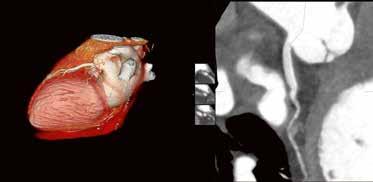

Neuartige High-DefinitionTechnologie: „Wie ein Mikroskop für den Neuroradiologen“

Die Alphenix Angiographiesysteme von Canon Medical können nun mit innovativer HD-Technologie ausgestattet werden. Mit dem weltweit ersten hochauflösenden Flachdetektor für die Angiographie sind kleinste Gefäße und Gefäßanomalien mit kleinsten interventionellen Devices besser behandelbar. Im Interview spricht Matthias Schmidbauer, Manager Sales Support X-Ray bei Canon Medical Systems, über die Vorteile der neuartigen HD-Technologie für neurovaskuläre Eingriffe.

Was zeichnet die Alphenix Angiographiesysteme mit der neuen HD-Technologie von Canon Medical Systems aus?

Diese neuartige Technologie ist das Ergebnis jahrelanger Forschungsarbeit, die wir in Zusammenarbeit mit führenden Kliniken, wie dem Gates Vascular Institute in Buffalo, geleistet haben. Es ist uns gelungen, den weltweit ersten hochauflösenden Flachdetektor für die dynamische Bildgebung in der Angiographie zur Marktreife zu führen. Die Auflösung des HD-Flachdetektors konnten wir auf außergewöhnliche

6,5 Linienpaare pro Millimeter steigern –

auf einen ca. doppelt so hohen Wert, verglichen mit konventionellen Systemen. Um jetzt auf Ihre Frage zurückzukommen, können damit kleinste Gefäße und Gefäßanomalien mit

kleinsten interventionellen Devices sicherer und schneller behandelt werden, was diese Technologie insbesondere für die Behandlung zerebraler Gefäßerkrankungen prädestiniert.

Wenn Neuroradiologen beispielsweise intrakranielle Aneurysmen mit dem endovaskulären Coiling-Verfahren behandeln, benötigen sie Sichtkontakt zur Läsion. Je besser sie die feinen, über einen Mikrokatheter in das Aneurysma vorgeschobenen Platinspiralen, die sogenannten Coils, sehen, desto präziser

HD-Flachdetektor

und zügiger können sie diese im Aneurysma packen und dessen Innenwand abdecken. Häufig muss die entfaltete Platinspirale zusätzlich noch durch einen Stent mit sehr feinem Drahtgeflecht gestützt werden, der ebenfalls genau zu platzieren ist.

Durch die Vergrößerungsmöglichkeit im HD-Modus können diese kleinen

Devices und Gefäßstrukturen auf dem Monitor klar dargestellt werden. Somit ist auch der Behandlungsfortschritt genauer nachvollziehbar. Der HDFlachdetektor funktioniert in diesem Zusammenhang wie ein Mikroskop für den Neuroradiologen. Es leuchtet ein, dass die HD-Technologie daher zu besseren Behandlungsergebnissen und höheren Überlebensraten führt.

Klinischer Fall: 11 mm Kavernöses Karotisaneurysma rechts; Behandlung mit LVIS-Blue-Stent und Coils; Bildgebung mit lateralem HD-Flachdetektor, 6 cm x 6 cm FOV, Fluoro-Modus.